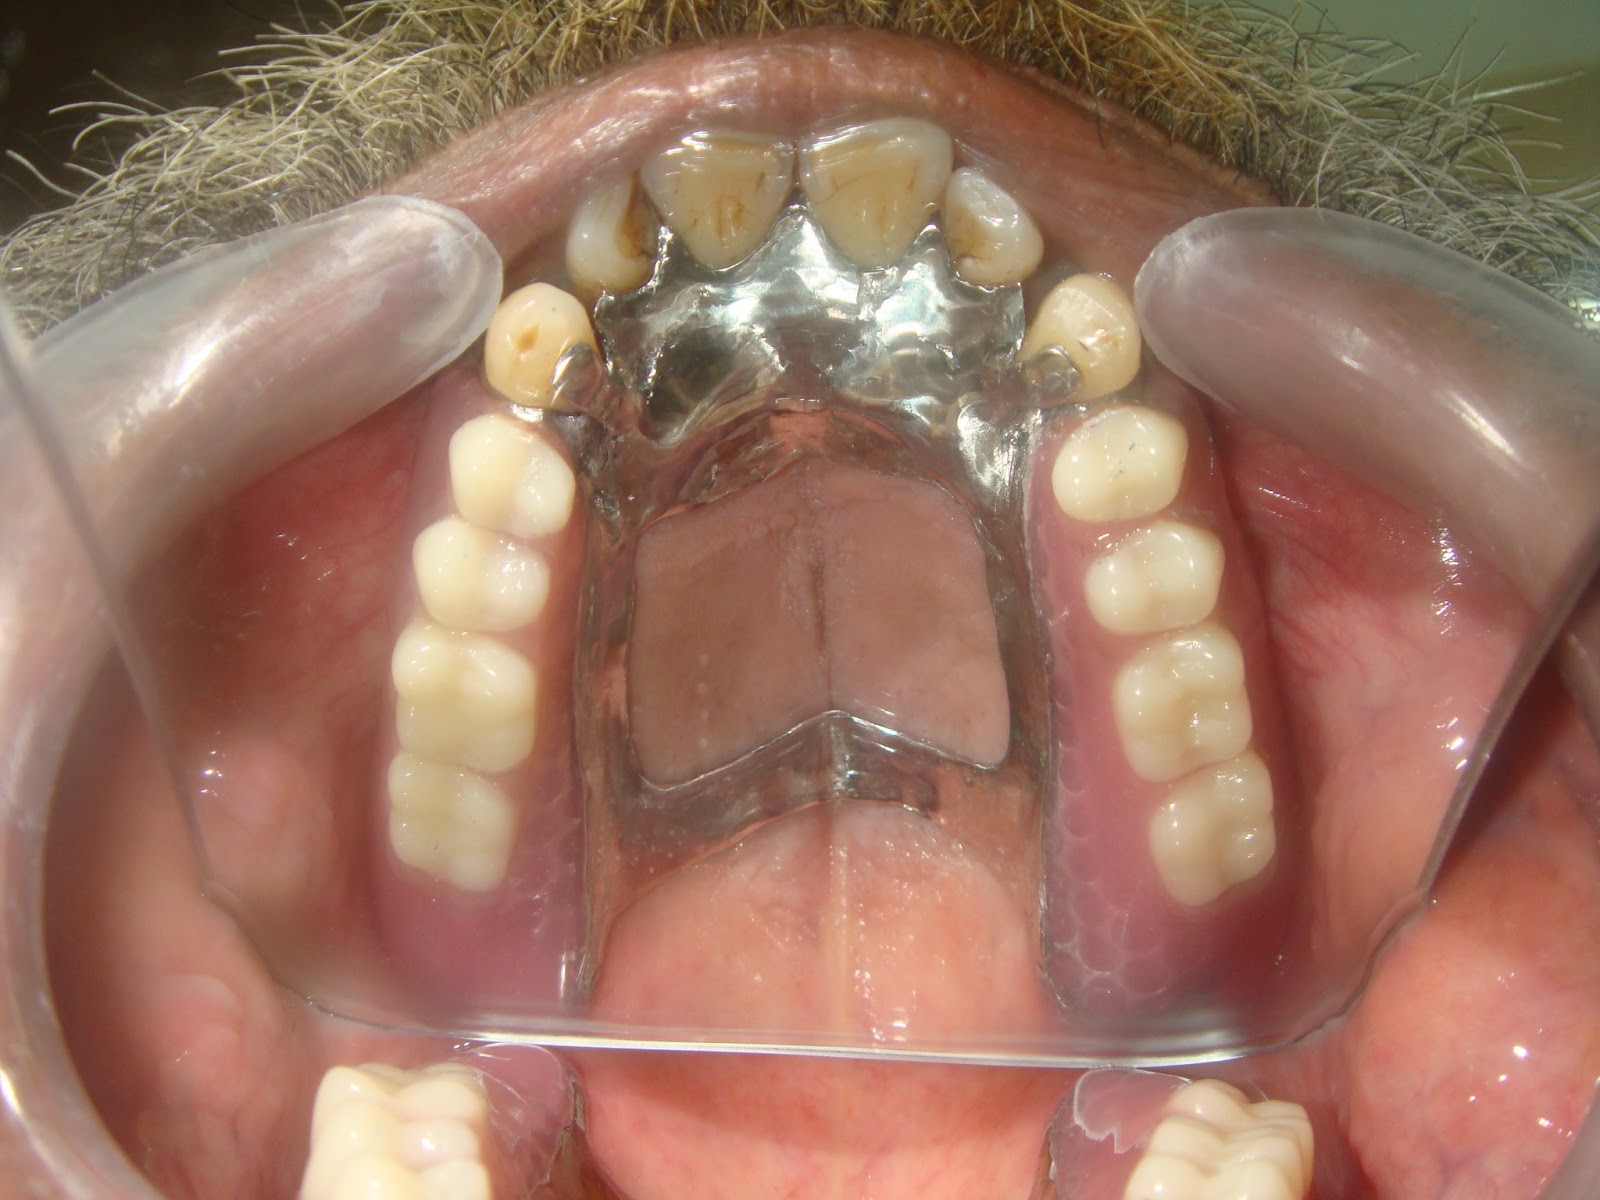

Cast Partial Denture Procedure . Cast metal partial dentures are the most common type of removable partial dentures. A partial denture that can be removed and replaced in the mouth by the patient. The removable partial dentures fabrication consists of six visits. Esthetics, mastication, occlusal support and convenience. You can take the partial denture out yourself, for cleaning and at. Partial dentures are made up of one or more artificial teeth held in place by clasps that fit onto nearby natural teeth. Preliminary impressions, diagnostic casts, and rpd design visit 2 : What is the procedure for having a partial denture? This gives the dentist an opportunity to find out all.

The removable partial dentures fabrication consists of six visits. Cast metal partial dentures are the most common type of removable partial dentures. You can take the partial denture out yourself, for cleaning and at. What is the procedure for having a partial denture? This gives the dentist an opportunity to find out all. Partial dentures are made up of one or more artificial teeth held in place by clasps that fit onto nearby natural teeth. A partial denture that can be removed and replaced in the mouth by the patient. Preliminary impressions, diagnostic casts, and rpd design visit 2 : Esthetics, mastication, occlusal support and convenience.

Cast Partial Denture Procedure Esthetics, mastication, occlusal support and convenience. A partial denture that can be removed and replaced in the mouth by the patient. The removable partial dentures fabrication consists of six visits. Preliminary impressions, diagnostic casts, and rpd design visit 2 : Partial dentures are made up of one or more artificial teeth held in place by clasps that fit onto nearby natural teeth. Esthetics, mastication, occlusal support and convenience. You can take the partial denture out yourself, for cleaning and at. What is the procedure for having a partial denture? This gives the dentist an opportunity to find out all. Cast metal partial dentures are the most common type of removable partial dentures.